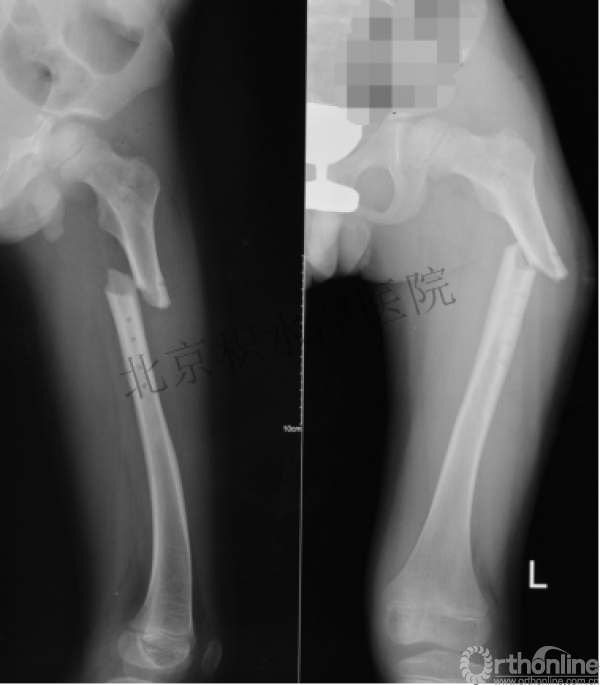

又过了4年!时间来到2015年

一年以后顺利愈合,实则危机四伏

数月后再骨折!牵引!

髋人字支具

外固定架术后一年

整整11年!是否治疗终结?

病人的付出?医生当反思!